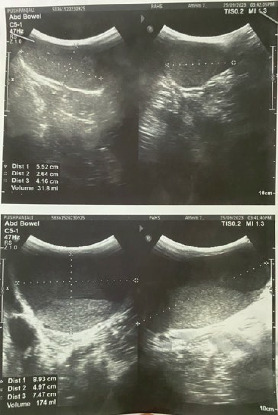

Sacrococcygeal teratomas are rare in adults, despite being common in infants. Adult presentations are often asymptomatic and may go undetected until complications arise. We report a case of a 20-year-old female with a long-standing sacral swelling. Imaging revealed a large, well-circumscribed mixed solid-cystic mass in the presacral region causing displacement of pelvic structures. Surgical excision of the tumor was done along with the surrounding rectal wall. Early surgical intervention is essential to prevent malignant transformation and optimize outcomes.